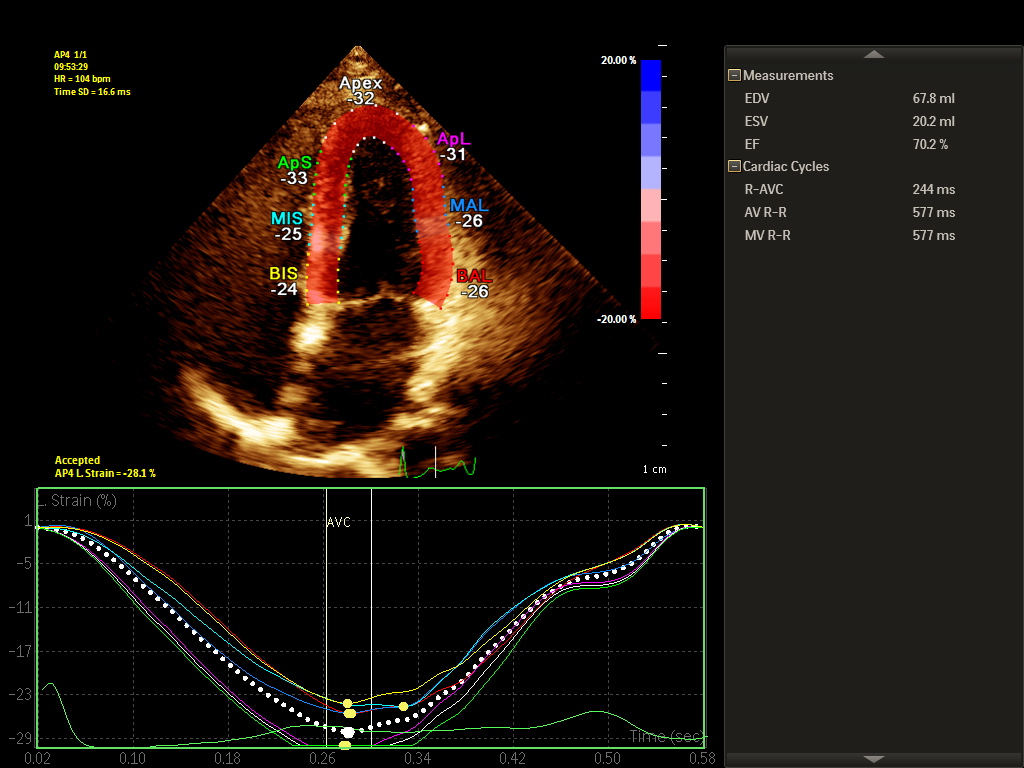

Ecocardiograma Bidimensional com Doppler Colorido

O Ecocardiograma com Doppler é um exame que avalia o coração através do ultrassom. Este exame é utilizado na avaliação dos pacientes com sopro cardíaco, palpitação, falta de ar, dor no peito ou portadores de diversas doenças cardíacas como infarto do miocárdio, insuficiência cardíaca, doenças das valvas, doenças congênitas, entre outras.

Avaliação das dimensões das câmaras cardíacas e da espessura de suas paredes (Avaliar o “tamanho do coração”).

Avaliação das valvas cardíacas.

Avaliação da função contrátil e do relaxamento do coração.

O paciente permanece deitado sobre a maca enquanto o médico realiza a avaliação com o ultrassom sobre o tórax do paciente.